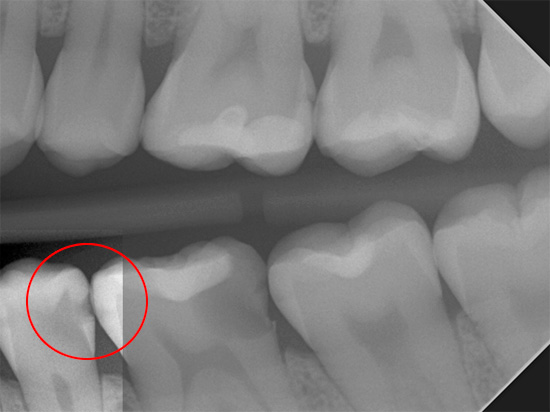

Le fotografie seguenti mostrano un'immagine radiografica di denti con una profonda cavità cariata nascosta:

I raggi X passano facilmente ammorbiditi con il tessuto della carie e nell'immagine viene visualizzata una macchia scura di una certa area in proporzione alla dimensione della cavità. Il messaggio di un tale "punto" in un quadro con una camera pulpare indica quasi sempre un'infiammazione del "nervo" e lo sviluppo di una complicazione della carie profonda: la pulpite.